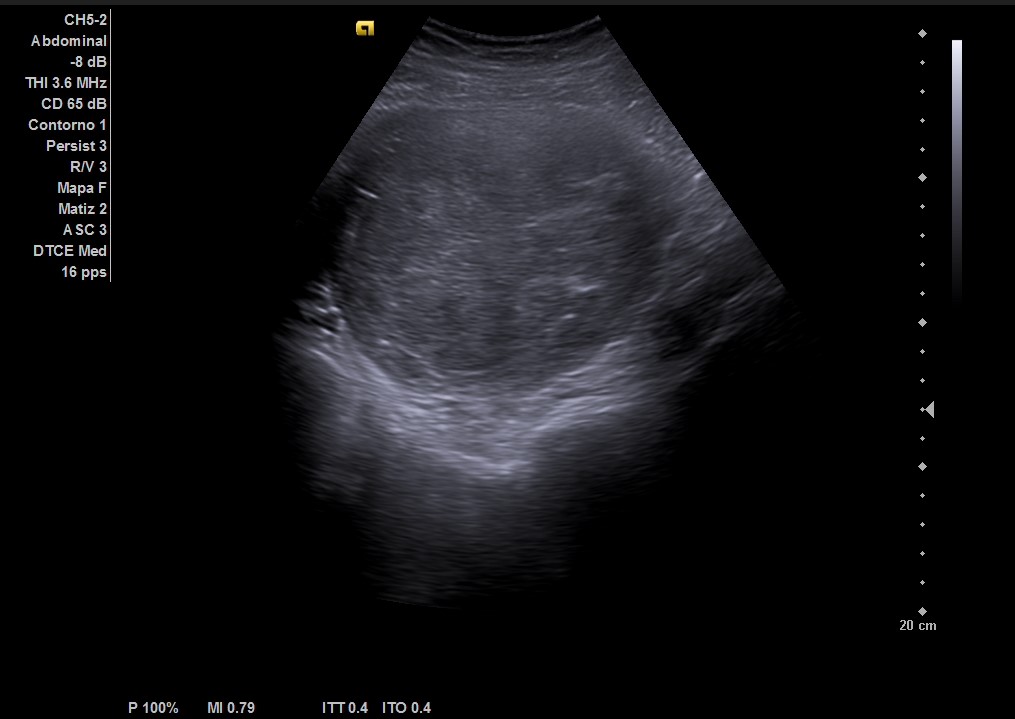

Ecografía abdominal: masa heterogénea de 10 x 10 cm dependiente de útero con vascularización periférica. No se observa la vejiga al estar repleccionada y desplazada por dicha masa. Se vuelve a hacer ecografía con vejiga llena y se observa cómo deforma la pared por efecto masa. Vejiga sin litiasis en su interior, no globo vesical.

La paciente es valorada en consulta de patología ginecológica. Le realizan una ecografía abdominal y transvaginal que describe: útero de unos 13 cm de histerectomía. Presenta varios miomas intramurales, destacando uno en cara posterior de 110 x 102 mm que parece contactar con cavidad endometrial sin desplazarla.